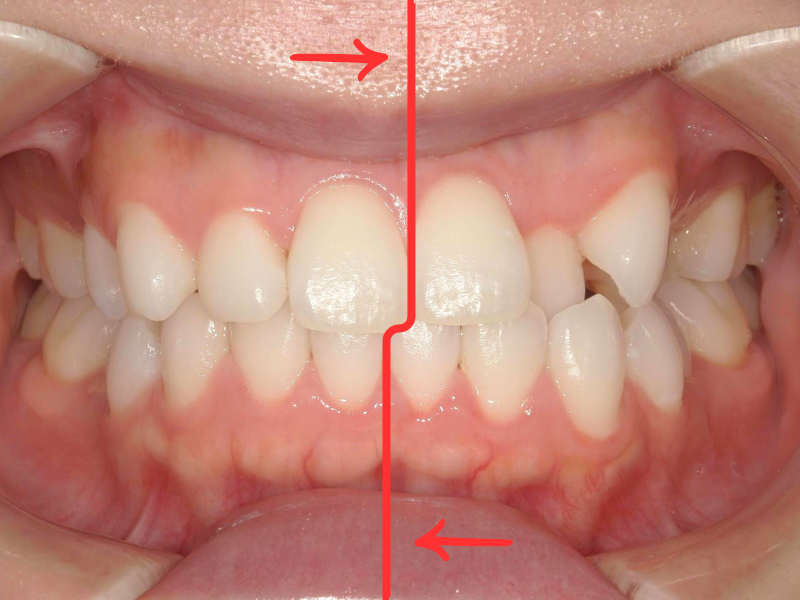

20代、女性、ワイヤー

| 施術内容 | 主訴:真ん中の線が合っていないのが気になる 詳細:ワイヤー矯正での歯並び改善 |

| 治療期間 | 18ヶ月(9/19現在 治療終了) |

| 費用 | ワイヤー矯正 60万円(税込660,000円) |